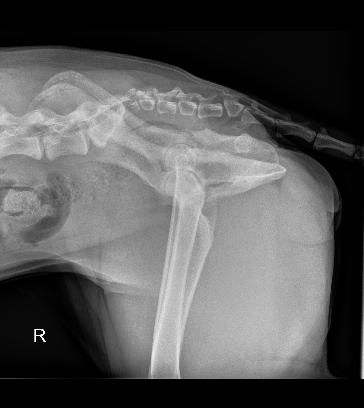

Ibought my first Rhodesian Ridgeback with my first paycheck out of Veterinary School in 1995 and have been in love with our smart and often naughty dogs ever since. Just before Christmas 2022, I lost my French imported Ridgie, “Grace” at 5 years and 1 week old to malignant visceral Mast Cell Tumor. She was my soul in a dog’s body, and as I watched our Great Dane “George” grieve for weeks, I decided to get another Ridgeback puppy. In February 2023, I went to a breeder and picked up little “Ruby”. She was a spunky little girl who could clearly keep up to her brothers. The puppies were crawling under a patio and exploring a big yard, so the small bump at the base of her back I thought was an injury. She was running around and seemed fine otherwise. I had a dog-trainer friend go with me, and so we flew home to Arizona with little “Ruby” between us on the plane. The breeder suggested that I could show her as she had great blood lines.

by Animal Biome (animalbiome.com) to help her alleviate the loose stools. We improved her diet, and added fish oils and other supplements. She strained to have a bowel movement from the time she got to our house as an 8 week old puppy, and has done so ever since. At first, she would walk around 10 m to complete her bowel movement. She almost “overflow defacated”. At about 10 weeks old she cried out as I was sitting on the floor playing with her and my hand bumped into her lower back. I took her to my hospital and x-rays of her back were done. She looked like a French Bulldog beyond her sacrum and into her tail. She had a pronounced wedge shaped coccygeal vertebrae (called hemivertebrae) in the location of her bump.

dog, and it appears she is not. Her latest X-rays show the first, third and fifth coccygeal vertebrae are actually hemivertebrae creating a really uneven tailset area. An MRI might be in her future to help identify the reason for the pain and prolonged defecation, but not yet. She is a ‘high tail kink’ dog at this time. Kinked tails are supposed to be innocuous. But, that is not the case here. Her pain is real. My family and I will care for her and offer her a performance life as part of our pack. We lovingly call her “Aunt Ruby” already. She has had chiropractic work done and has had sporadic doses of anti-inflammatory medication if she is hurting.

Ruby in Stack Kink in tailset and her xrays